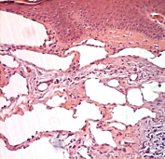

Cystic hygroma is the rare congenital lesion. This is a cystic variety of lymphangioma. Cystic hygroma arising outside of the cervicofacial, thoracic, and abdominal areas are extremely rare. Wrist is a very rare site for occurrence of cystic hygroma. Presentation depends on site of location of cystic hygroma. A case of cystic hygroma of wrist in a child is reported. This child presented with painless swelling of left wrist. Excision of cyst was done. This is first case report of literature reporting occurrence of cystic hygroma on wrist.